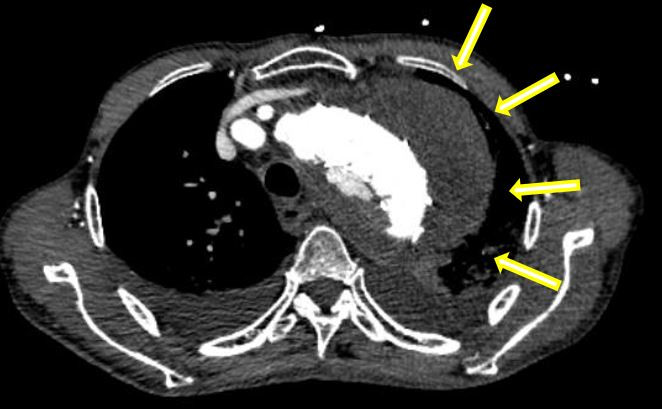

巨大假性动脉瘤压迫左肺(箭头示)

在患者转运过程中,血管外科急诊团队、影像科、麻醉科、胸心外科、导管室、输血科等相关科室已着手做好了急诊相关预案。从患者的急诊CTA上可以看到原有的胸主动脉支架因血流动力学影响,出现了近端Ⅰ型内漏,大量血液经由支架与主动脉间的缝隙进入假性动脉瘤腔内,左侧胸腔出现大量血肿,甚至出现了少量的心包积液。急诊血常规显示患者血红蛋白才66g/L,颜老爷子已出现烦躁不安等谵妄表现,为保障手术安全,团队立即联系输血科郑春盛主任,有力地保障了患者术中用血。

术前:双侧胸腔大量积血,双肺受压(箭头示)